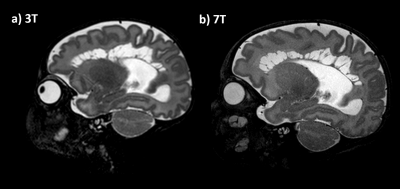

SVR of T2w images provided increased tissue contrast and SNR by combining multiple images into single 3D volumes while correcting for motion, as demonstrated in Figure4.

In our small cohort, we found that visualisation of anatomy was better appreciated at 7T on T2w imaging in comparison to 3T, notably in the hippocampus, cerebellum vermis, and cortical folding. This may be a direct result of increased SNR. SVR was found to be helpful in both ensuring full multi-planar visualisation and in removing artefacted slices. In general, the 7T SVR results provided more details than the corresponding 3T reconstructions.

Figure 4: SVR of the T2 images additionally provided correction for head motion during acquisition and further increases in tissue contrast and SNR. The top row shows the Native Data (axial slices) whereas the bottom shows the SVR isotropic volume.